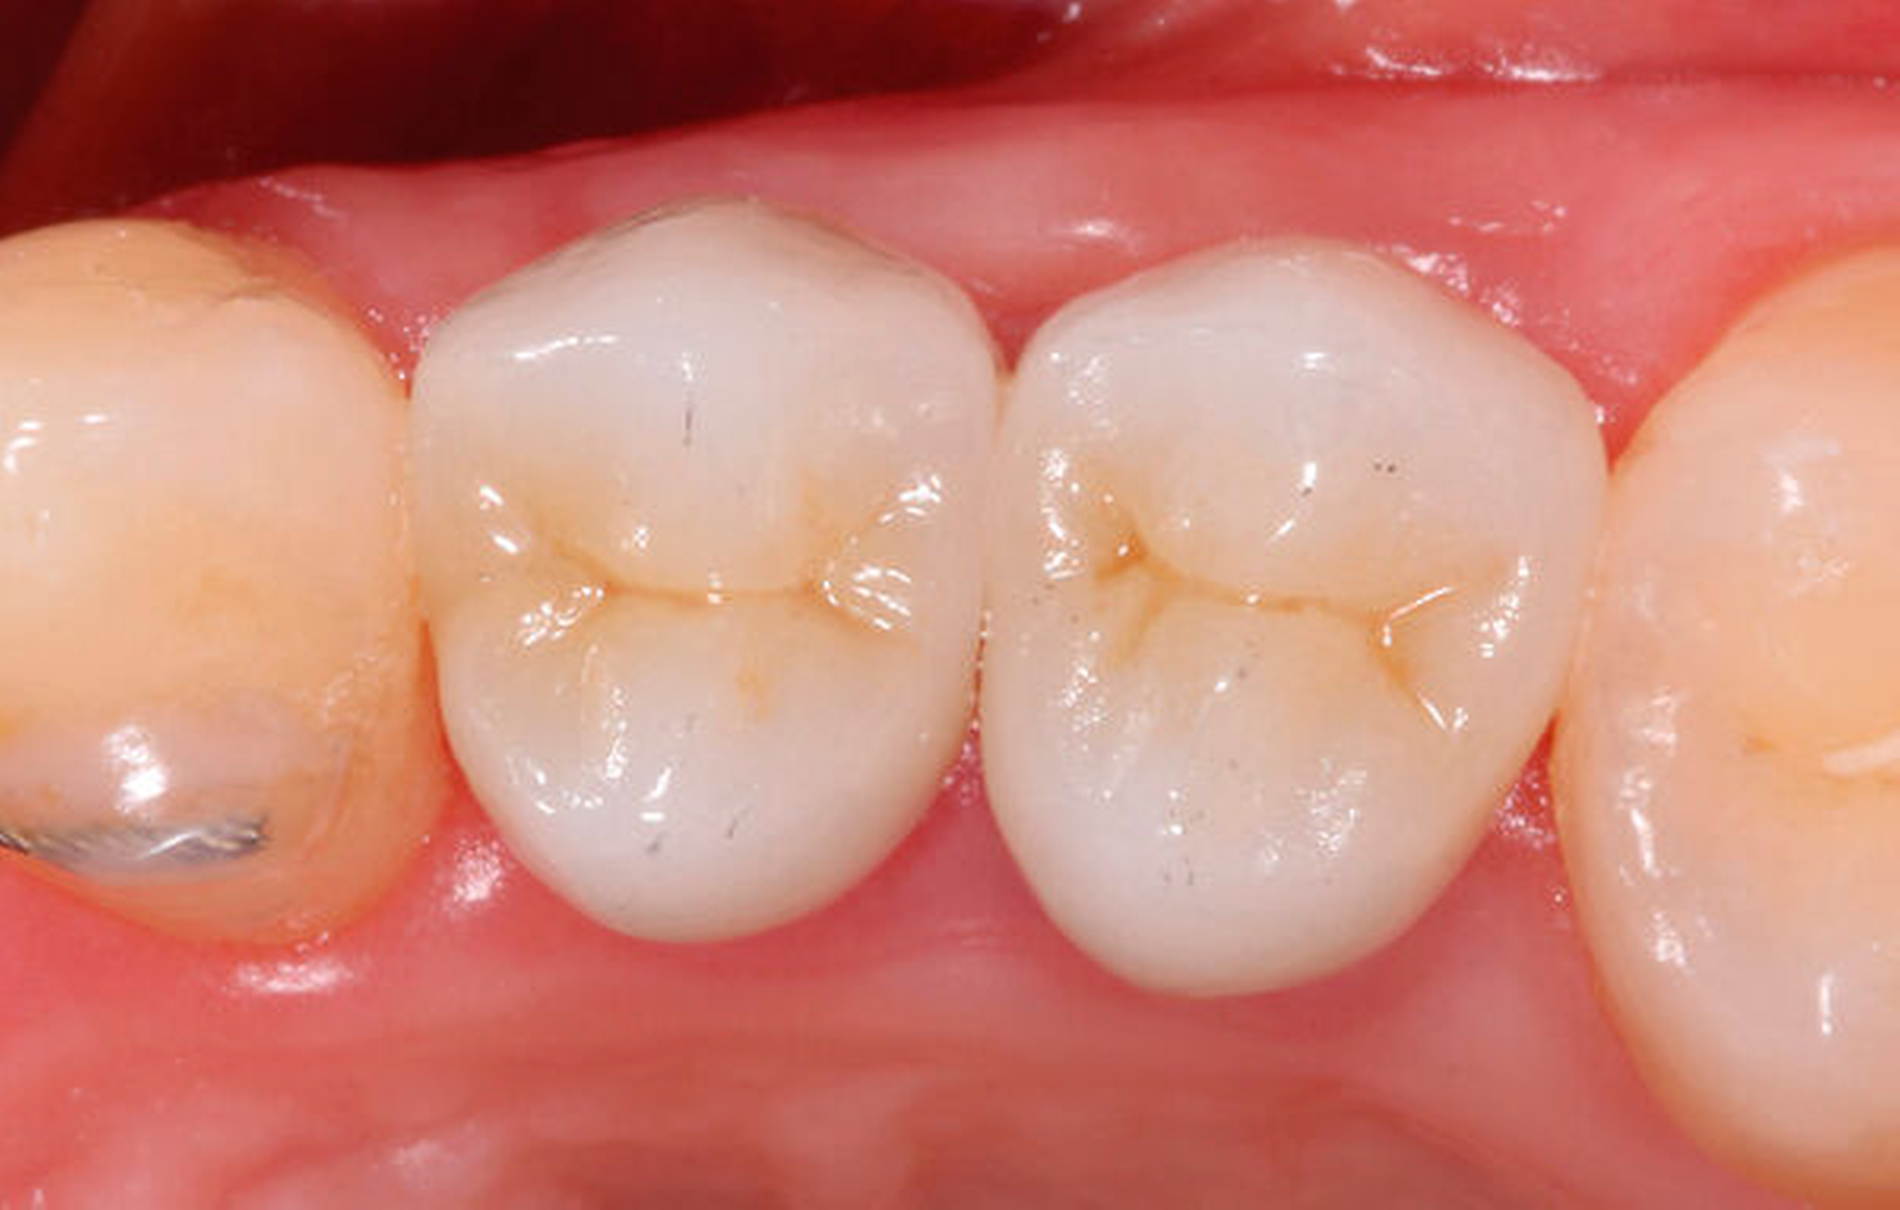

Als Vorteil der chirurgischen Extrusion im Vergleich zur chirurgischen Kronenverlängerung wird das deutlich vorteilhaftere ästhetische Resultat mit Erhalt von Weichgewebe und Papille angegeben [Llaquet et al., 2021]. Diese Gewebe werden geschont und erfahren keine Traumata, wie dies bei einer chirurgischen Kronenverlängerung unvermeidbar geschieht [Behring et al., 2017; Lanning et al., 2003]. Indiziert ist die Extrusion vor allem bei einwurzeligen Zähnen in ästhetisch relevanten Bereichen. Biologisch betrachtet liegen solide und langzeitstabile Resultate zu dieser Technik vor. Einer aktuellen Übersichtsarbeit zufolge, basierend auf elf klinischen Studien, kann ein Behandlungserfolg mit parodontaler Heilung der Wurzel in 95 bis 100 Prozent der Fälle nach chirurgischer Extrusion erwartet werden [Plotino et al., 2020]. Eine weitere Übersichtsarbeit fokussiert auf die Häufigkeit von Komplikationen nach chirurgischer Extrusion. Den verfügbaren Daten zufolge liegt das Risiko für Zahnverlust bei fünf Prozent, das für progressive Wurzelresorptionen bei drei Prozent. Ein marginaler Knochenabbau ist ebenfalls eine seltene Komplikation (weniger als vier Prozent der Fälle). Nicht progressive Wurzelresorptionen werden mit circa 30 Prozent zwar recht häufig beobachtet, diese sind allerdings selbstlimitierend und gefährden nicht den Zahnerhalt [Elkhadem et al., 2014].

In einer eigenen klinischen Studie mit einer mittleren Beobachtungszeit von 3,1 Jahren wurde eine erfolgreiche Extrusion bei 47 von 51 Zähnen evaluiert [Krug et al., 2018]. Zusammenfassend gilt, dass kaum negative Folgen, die den Zahnerhalt ernsthaft gefährden könnten, mit dieser Technik assoziiert sind. Die biologische Komplikationsrate kann trotz der vermeintlichen Invasivität der chirurgischen Extrusion als eher gering eingestuft werden.